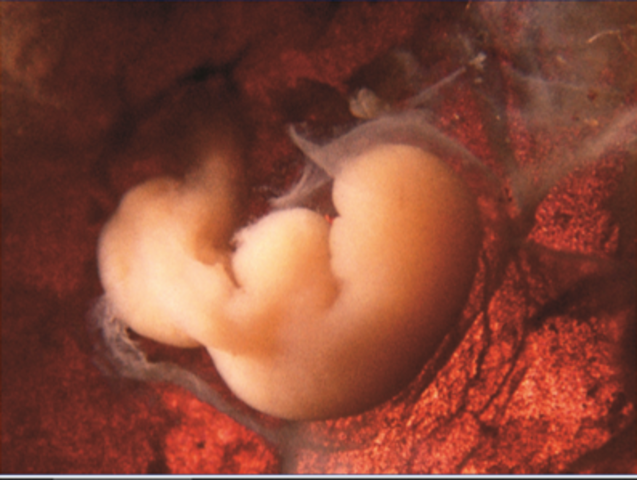

• 4 a Semana

4 a Semana

Período de transición entre la formación del embrión (embriogénesis) y la de los órganos (organogénesis) del futuro bebé. Los primeros latidos cardíacos se manifiestan hacia el 23.º día. El embrión adquiere su forma definitiva:El embrión flota en medio de la cavidad amniótica, unido a la parte externa del huevo por el cordón umbilical, que se está formando. Al final de este primer mes, el embrión mide 5 mm.